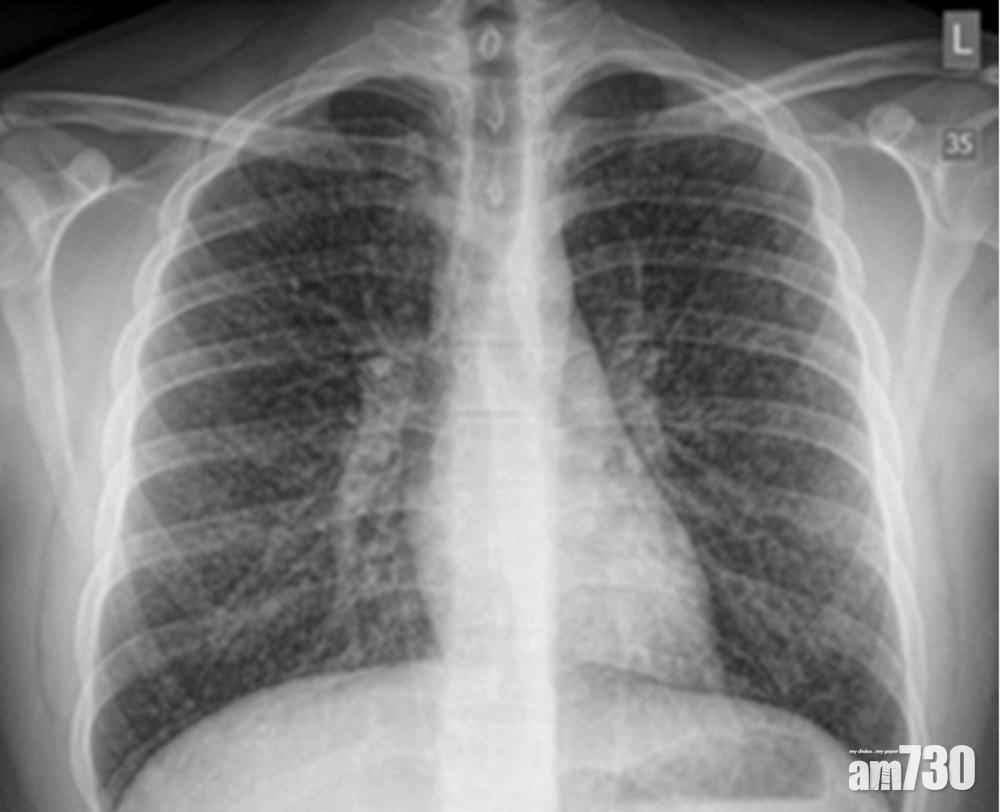

外國曾有人因吸食電子煙,令肺部「花晒」。